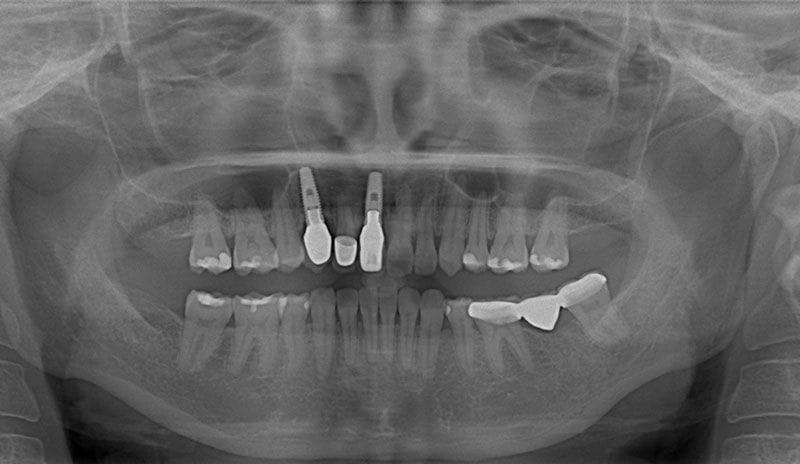

術後X光片